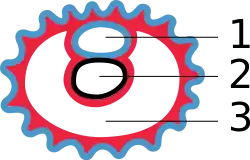

Embryo 3 weken oud (vanaf de bevruchting) 1 - vruchtzak of amnionholte, 2 - dooierzak, 3 - chorionholte

1 - vruchtzak of amnionholte, 2 - dooierzak, 3 - chorionholte De vroege vorming van de allantois en differentiatie van de hechtsteel. 1 vruchtzak of amnionholte, 2 hechtsteel, 3 allantoïs, 4 dooierzak, 5 chorion. Het chorion omhult de chorionholte.